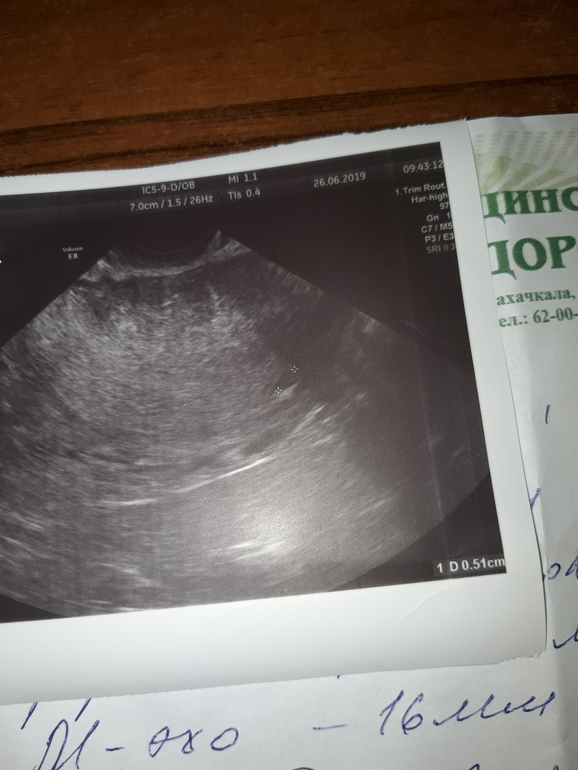

Девочки,понесло меня короче на повторное узи,муж настоял,так как вчера ночью сильно болел правый бок,не спала всю ночь. В общем,2 дня назад на узи видели пятнышко размером 3-4,сегодня это пятнышко было уже побольше,5 с лишним мм,врач узи говорит что непонятно что это,спросила про тесты,так я говорю они почти сравнялись,ну ладно посмотрела желтое тело и нашла размером 22,крутила вертела датчиком,начала говорить что на пя не похоже и возможно пя еще в трубе,девочки как это??? Я ей говорю как так,тесты то не пустые значит где то да прикрепился плод,говорю ей ведь хгч вырабатывается после имплантации,на что она мне говорит что хгч вырабатывается с момента зачатия🙄🙄🙄что за бред? Спросила есть ли задержка,да уже второй день. На что она меня вновь спрашивает принимаю ли я какие нибудь гормоны,отвечаю что пью дюфастон,а она мне возмущенно "конечно на нем у вас месячные не пойдут"🤦🏼♀️.Вопрос,почему они у меня должны пойти при положительных тестах и довольно не плохих показателях узи??? Девочки то ли я туплю то ли много знаю,что это за бред с хгч,везде ведь пишут что он вырабатывается после имплантации,как это все понимать? Добавлю,в предыдущие беременности когда я ходила на узи мне врачи так же говорили когда пя не видели в матке,типо еще по трубам идет. Загляните пожалуйста на снимок,может кто что поймет,еще в прошлую пятницу в матке ничего не было а на понедельник обнаружилось это черное пятно и на сегодня оно увеличилось,что это еще может быть если не плодное яйцо